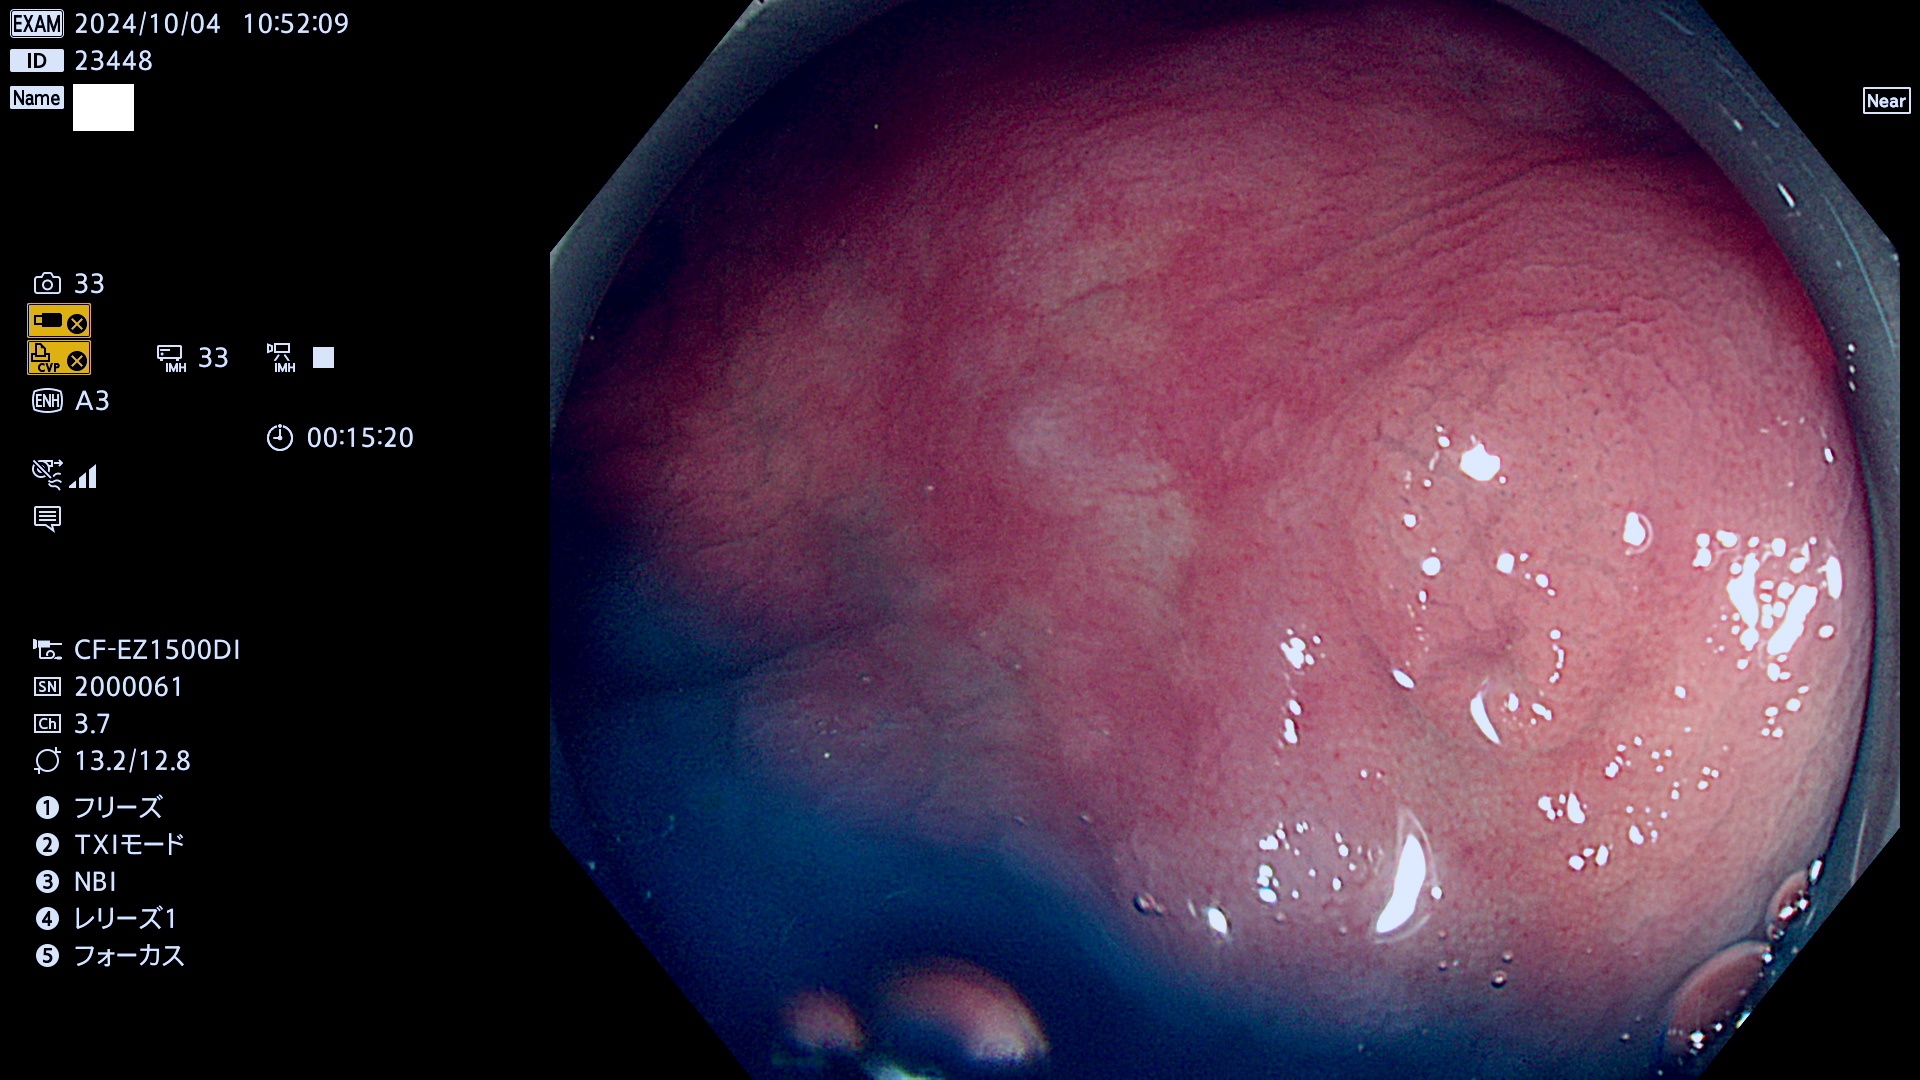

今週のUb、Uc型腺腫

完全に平坦な物をUb、陥凹している物をUcと呼びます。最も発見が難しく危険な病変です。

毎週の検査(木・金・土・日)に発見されたUb、Uc型・腺腫を、その週の日曜の夜にUPし1週間、提示します。

抽出の対象期間 2024年10月3日〜10月6日の4日間(48件の検査)9件 (9/48=18%)